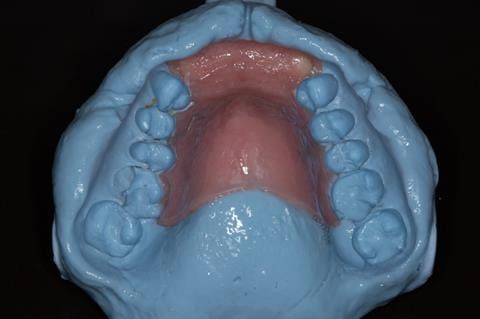

Provision of a maxillary cobalt chromium based partial denture/protective occlusal splint in a heavily restored dentition

- Extract the upper 2-2 teeth and replace with an interim acrylic based partial denture. Reline the interim denture over 9 - 12 months, replacing with a definitive cobalt chromium based partial denture. The definitive denture would ideally be designed as an occlusal protective splint to reduce the the potential for mechanical wear and breakages of the moderately/heavily restored maxillary dentition. In addition, should further upper teeth require extraction they could be added on to the denture cobalt chromium framework - therefore a new prosthesis would not be required as future teeth are lost. This option would produce an excellent aesthetic outcome. This is the option the patient chose to have.

Following consultation and second discussion appointment the patient chose to have option 3 namely, a maxillary cobalt chromium based partial denture/protective occlusal splint. The clinical situation and treatment process is shown in detail below with photographs. The patient was successfully rehabilitated with this and her quality of life considerably improved. The clinical work was provided by Finlay and the technical work by Rowan.